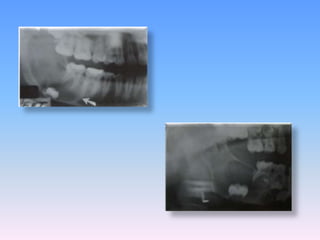

unilocular, well defined, radiolucent lesion in the left mandibular horizontal and

ascending ramus. The third molar is impacted and displaced towards the lower

border